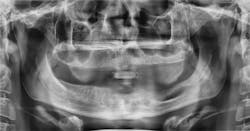

Figure 3 shows a patient in his 60s who had a third-molar extraction. He developed an 11 mm pocket on the distal of No. 31 after the extraction of No. 32 and never regained the bone associated with this area. The patient had no pain, but the tooth did have mobility. The surgeon waited to assess the bone in the distal area of No. 31, but since the area never filled in, the tooth was eventually extracted. This depicts an example of bone loss that was never regained or filled in with healthy bone.

Figure 3: Chronic bone loss in the area of No. 31. Extraction occurred without subsequent bone formation. Courtesy of Carol Perkins, BA, RDH.